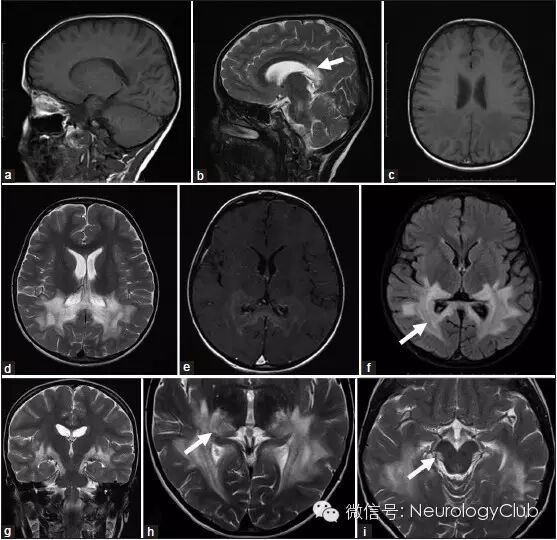

6岁男孩,进行性言语理解障碍,学习成绩下降,斜视伴视觉缺损4月。一般查体提示中度低血压以及皮肤色素沉着。神经系统查体提示理解困难,双眼视力下降,共轭凝视不良,双侧辨距不良,步态不稳。脑脊液蛋白升高(1.82g/L)。头颅MRI提示大脑后部和脑干异常信号。清晨皮质醇水平降低(21nM)。促肾上腺皮质激素兴奋试验证实肾上腺功能不全。极长链脂肪酸分析提示C26:0/C22:0和C24:0/C22:0比值升高。神经遗传学检测提示ABCD1基因突变。

(A:黑水像提示大脑半球后部对称融合性白质高信号病灶;B-C:T1增强可见对称性的线状强化,被认为是中间炎症区,其在黑水像和ADC上信号较其余病灶要低;D:MRS提示NAA下降,Cho升高,可见乳酸峰)

(a:T1WI;b:T2WI;c:T1WI;d:T2WI;e:T1+C;f:FLAIR;g-i:T2WI)